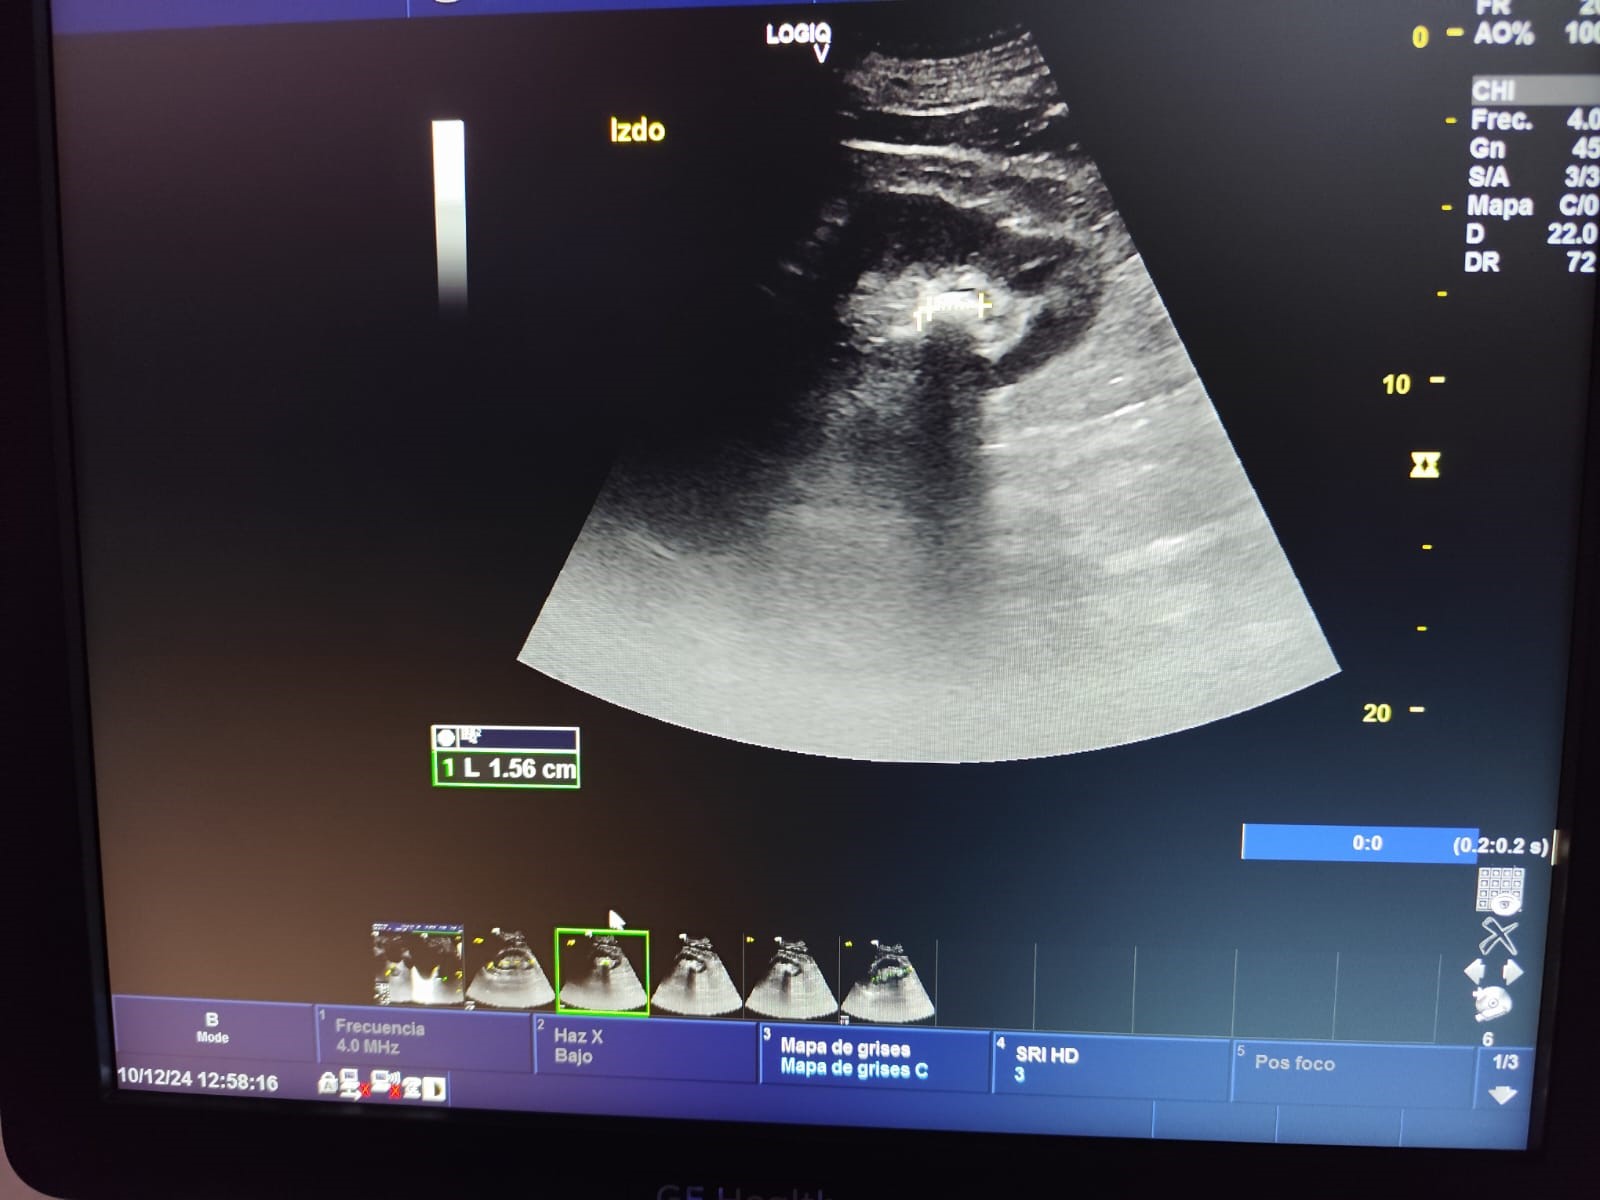

Descripción de los hallazgos ecográficos y las imágenes más relevantes para la resolución del caso

Ecografía en atención primaria (POCUS): Ecografía del riñón izquierdo: Litiasis de 1.4 cm en polo inferior, morfología y tamaño normales. Resto sin alteraciones.

Juicio clínico: Litiasis renal en riñón izquierdo, sin signos de hidronefrosis u otra complicación.

Realiza una nueva consulta por hematuria, sin aportar resultados de la prueba de imagen ya que se encuentra pendiente, por lo que se efectúa ecografía clínica en el Centro de Salud. El paciente realiza una videograbación del procedimiento ecográfico con el propósito de compartirla en la consulta de Urología, donde tras observar los resultados se remite a Litotricia Extracorpórea por Ondas de Choque.